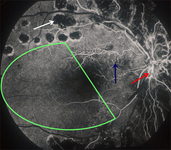

Fluorescein angiography in proliferative diabetic retinopathy. Vascular component of fibrovascular proliferation (red arrows), capillary non-perfusion (yellow arrow), laser burns (green circle)

Courtesy of Moorfields Photographic Archive; used with permission